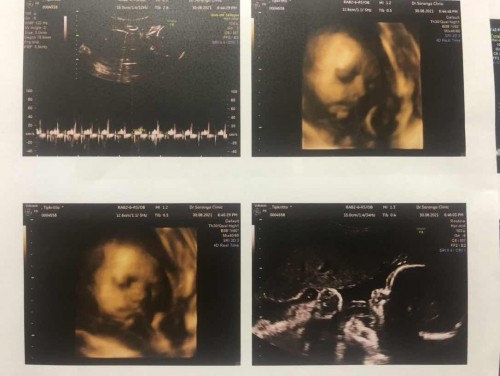

ตอนนี้น้อง 32 สัปดาห์ พึ่งซาวด์มาเมื่อวานค่ะ พบปัญหาน้ำคร่ำน้อย อยากทราบว่าเป็นอันตรายกับลูกไหมค่ะ น้ำหนักลูกต่ำกว่าเกณฑ์ไหมค่ะ 1600 กรัมค่ะ

Đọc thêmเรื่องน้ำคร่ำ น้อย อันตรายค่ะแม่ เพราะน้องต้องอยู่ในน้ำคร่ำ แต่ดื่มน้ำบ่อยๆ แม่น่าจะคลอดวันใกล้ๆเรา ไม่ต้องซีค่ะ เรื่องน้ำหนักลูกยังอยู่ในเกณฑ์ ไม่น้อยไป เพราะเราซาวด์มาเมื่อวันจันทร์ 1600 กรัม 32วีค หมอบอกปกติค่ะแม่ ดื่มน้ำเยอะนะคะ

บ้านนี้ 32+1 สัปดาห์ อัลตราซาวด์เมื่อวาน 2,362 กรัมแล้วค่ะ น้ำคร่ำน้อยก็เป็นภาวะเสี่ยง ให้คุณแม่ดื่มน้ำเยอะๆ พักผ่อนมากๆ นะคะ อย่าทำงาน กินนมกินอาหารโปรตีนเยอะๆ ช่วงอายุครรภ์หลังๆ น้ำหนักลูกจะเพิ่มมากขึ้นค่ะ